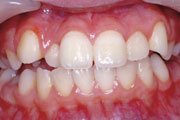

症例1:乱杭歯(叢生)

症例2:乱杭歯(叢生)